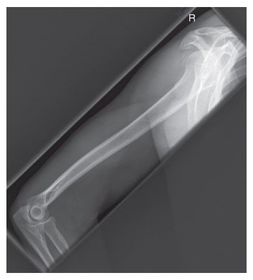

Which projection/position is this? PA Lateral Humerus

Which projection/position is this? AP External Humerus ________________________ Epicondyles are parallel to IR

Which projections/positions are these? (top->bottom) TOP: Scapular Y-View _________________________ BOTTOM: AP External Rotation (greater tubercle in profile)

Projection/position? Lateral Humerus